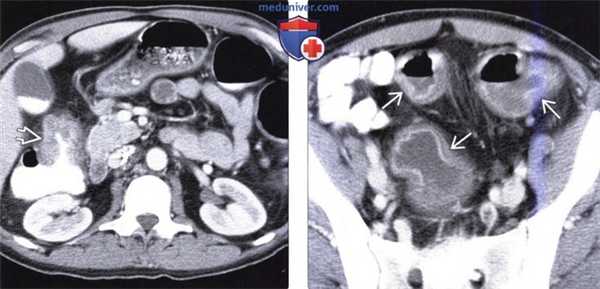

(Слева) На КТ у мужчины 49 лет, у которого снизился вес тела и развилась анемия, а также периодически возникала диарея слизистого характера, определяется циркулярное образование мягкотканной плотности, вызывающее сужение просвета восходящей ободочной кишки, верифицированное как первичный рак.

(Справа) На КТ у этого же пациента определяются признаки панколита: повышенное накопление контраста слизистой оболочкой и подслизистый отек. Длительно существующий язвенный колит является предрасполагающим фактором рака ободочной кишки.

о При язвенном колите риск возникновения колоректального рака выше, чем при болезни Крона:

- Ежегодная заболеваемость составляет 10% после первых десяти лет жизни с язвенным колитом

- Язвенный панколит наблюдается у 75-80% пациентов, страдающих раком ободочной кишки

- Множественный рак: в 25% случаев язвенного колита

Потенциально смертельным осложнением является токсический мегаколон, характеризующийся дилятацией ободочной кишки вне наличия обструкции как минимум до 6 см, а также признаками системной интоксикации (Sheth и LaMont, 1998). Изменениями, типичными для этого состояния, являются дилятация ободочной кишки, отсутствие гаустр, часто в сочетании с истончением стенки и нечетким узловым «рисунком» внутреннего края кишки при обзорной рентгенографии и КТ (Thoeni и Cello, 2006). Панколит и хронический язвенный колит ассоциированы с повышенным риском колоректального рака. Так, плоский или инфильтративный рак этой локализации трудно обнаружить на ранних стадиях при ирригоскопии с двойным контрастированием и даже при колоноскопии. КТ-признаками, позволяющими предположить наличие сопутствующей опухоли, являются выраженное асимметричное утолщение стенки и отсутствие дифференцировки ее слоев (Thoeni и Cello, 2006; Gore et al, 1996).